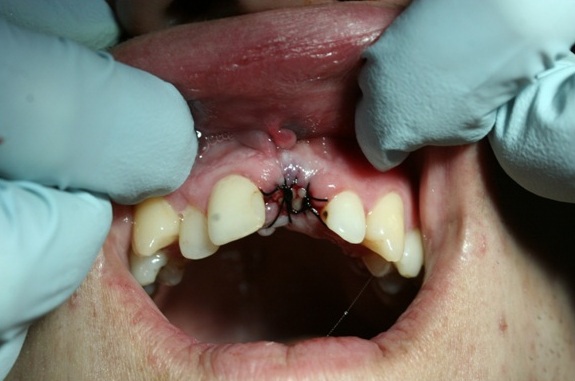

Patient K. (25 years old) turned to the clinic complaining about the aesthetic look of his 21st tooth.

Chronic periodontitis of the 21st tooth (Photo 1 and 2).

The examination found a sinus tract with an active inflammatory symptomatology. The endodontic treatment failed to give any positive results. There was made a decision to extirpate the 21st tooth along with simultaneous placement of Alpha Dent Implant with its diameter of 5 mm, 13 mm long and closure of soft tissue defects with PRP membrane. The surgery was carried out without immobilization of mucosa-periosteal graft making it possible to attain a good aesthetic look of the gingival edge and harmonious “rose-and-white” ratio.